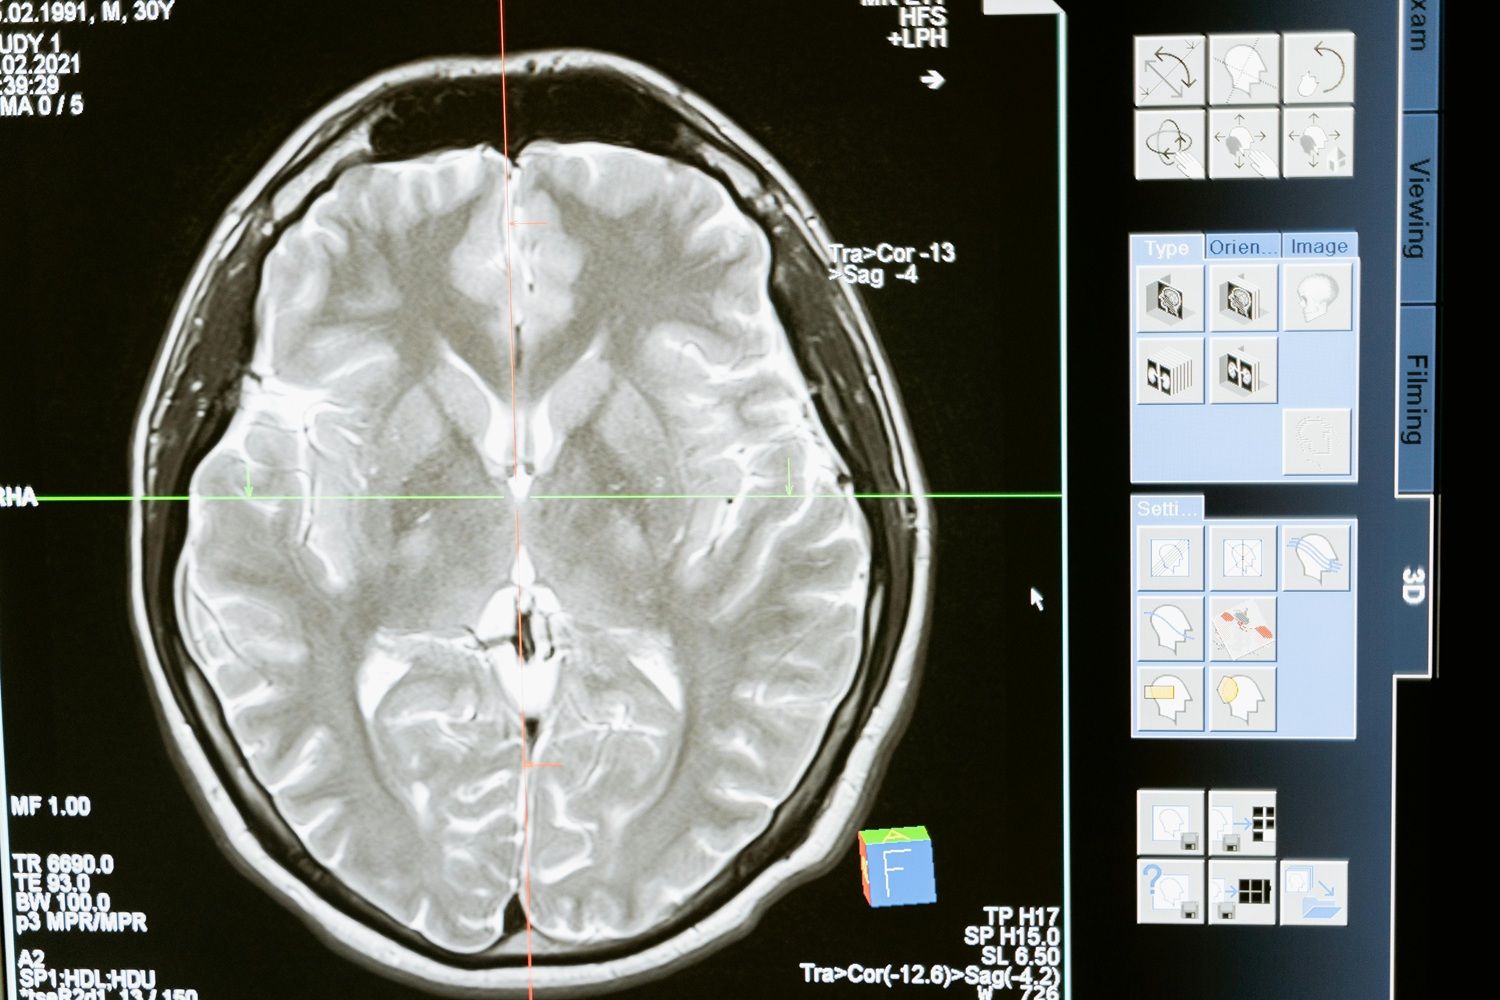

Pesquisas recentes têm aprofundado a compreensão sobre esses efeitos opostos. Um estudo da Universidade do Texas, publicado no Journal of Clinical Medicine em outubro de 2024, mostrou que níveis mais altos de HDL podem ter efeito neuroprotetor. Em exames de imagem realizados com 1.800 adultos, aqueles com mais HDL apresentaram maior volume de matéria cinzenta — o que pode indicar preservação cognitiva ao longo do envelhecimento, inclusive entre pessoas com o gene ApoE4, associado ao Alzheimer.

O colesterol cerebral é produzido localmente e não atravessa facilmente a barreira hematoencefálica, o que o torna diferente da gordura que circula pelo restante do corpo. Apenas alguns derivados, como o 24S-hidroxicolesterol, conseguem ultrapassar essa barreira.

Essa relativa separação protege o sistema nervoso de flutuações rápidas nos níveis lipídicos, mas não impede totalmente que problemas sistêmicos influenciem o cérebro. Indivíduos com síndrome metabólica, por exemplo, tendem a apresentar menor volume cerebral e pior desempenho cognitivo. “Embora as gorduras saudáveis sejam cruciais para a função cognitiva, ter baixos níveis de HDL associados a outros problemas metabólicos já foi ligado a resultados piores em testes”, observa Rached.